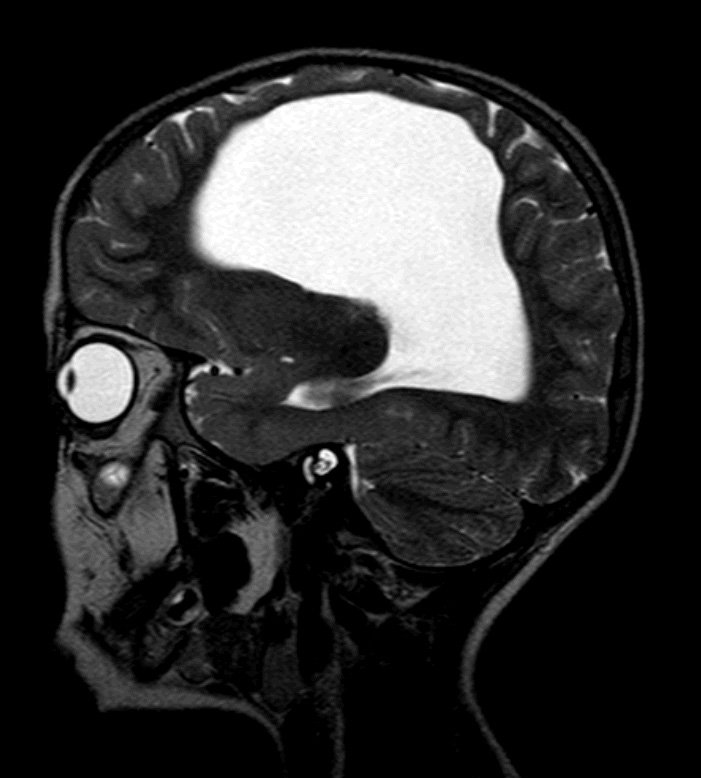

Rinorreia Crónica: Rinite ou Algo Mais?

Criança, Diagnóstico por Imagem, Rinorreia, encefalocelo/diagnósticoDownloads